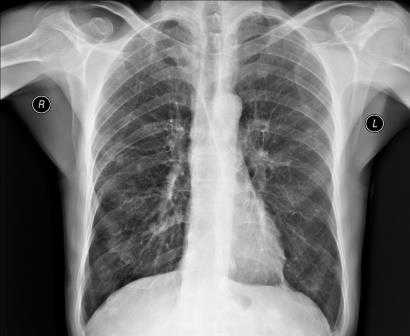

Органы и ткани человека по-разному реагируют на ионизирующее излучение: чем выше их плотность, тем светлее на снимке объект. Выполнение рентгенографии грудной клетки позволяет изучить мягкие ткани, кости этой части тела и анатомические структуры, находящиеся в исследуемой полости (легкие, плевру, средостение).

В зависимости от показаний пациенту может быть назначен обзорный или прицельный рентген грудного отдела. В первом случае получают изображения всех органов грудной клетки. На снимке обзорной рентгенографии хорошо видны дыхательные пути, лимфоузлы, сосуды, бронхи, трахея, легкие и сердце. Прицельная рентгенография направлена на исследование конкретного органа или его части и обеспечивает оптимальное изображение патологического очага для диагностики.

Во время расшифровки полученного рентгеновского снимка, прежде всего, оценивается качество изображения, а значит, и насколько правильно осуществлена процедура. Если рентгенография была сделана в неверной проекции и снимок имеет неточности, то заключение на его основании сделать достаточно сложно. При рентгене легких, например, оценивается размер легких, их форма, структура тканей и легочных полей, состояние воздушности и расположение внутренних органов.

Если у пациента пневмония, на снимке будут видны ярко выраженные отклонения от нормы - интенсивные дополнительные ткани как на прямой, так и на боковой рентгенограмме. Присутствие на снимке особой прикорневой формы, напоминающей по виду крылья бабочки, говорит о венозном застое в области малого круга. На отечность легочной ткани будут указывать неравномерные хлопьевидные затемнения на изображении.

Рентген грудной клетки дает возможность изучить костные структуры (ребра, грудину, позвоночник), легкие, плевру, бронхи и трахею, сердце и средостение, а также оценить состояние мягких тканей этой области.

Снимки обычно делаются в заднепередней и левой боковой проекциях. В заднепередней проекции благодаря уменьшению расстояния между сердцем и рентгеновской пленкой изображение сердца получается более четким и менее искаженным, чем в переднезадней. У лежачего пациента можно воспользоваться передвижным рентгеновским аппаратом, но он позволяет делать снимки только в переднезадней проекции.

Нормальная картина

В норме на снимках, выполненных в заднепередней проекции, ширина грудной клетки по меньшей мере в 2 раза превышает поперечный размер сердца. В то же время в переднезадней проекции относительные размеры и положение сердца могут быть другими; возможно усиление тени сердца и дуги аорты. Когда исследование проводится с контрольной целью, рентгенограммы грудной клетки должны подтверждать правильное положение катетеров и водителей ритма.

Изменение формы сердца обычно заключается в увеличении левого или правого желудочка, левого предсердия или даже нескольких полостей. При увеличении левого желудочка в заднепередней проекции левая граница сердца становится круглой и выпуклой с боковым расширением в своей нижней части, а в боковой проекции определяется выбухание левого желудочка кзади. При увеличении правого желудочка в заднепередней проекции наблюдается вторичное изменение левой границы сердца за счет расширения тени легочной артерии, а в боковой - расширение тени выносящего тракта правого желудочка. При увеличении левого предсердия его плотность на рентгенограмме в заднепередней проекции увеличивается вдвое, левая граница сердца сглаживается, левый главный бронх смещается кверху. В редких случаях правая граница сердца над проекцией правого желудочка расширяется кнаружи. В боковой проекции определяется выбухание левого предсердия кзади. Начальными признаками застоя в малом круге кровообращения на снимках, сделанных в заднепередней проекции, являются расширение тени легочных вен в верхнебоковой части корней легких и сосудистые тени, расположенные горизонтально вдоль нижней части правой границы сердца. Хроническая легочная венозная гипертензия приводит к формированию рисунка по типу оленьих рогов (из расширенных верхних и нормальных или суженных нижних легочных вен). При остром отеке легких увеличение плотности в центре легочных полей может по форме напоминать бабочку. Интерстициальный отек легких может напоминать снежные хлопья на фоне легочных полей.